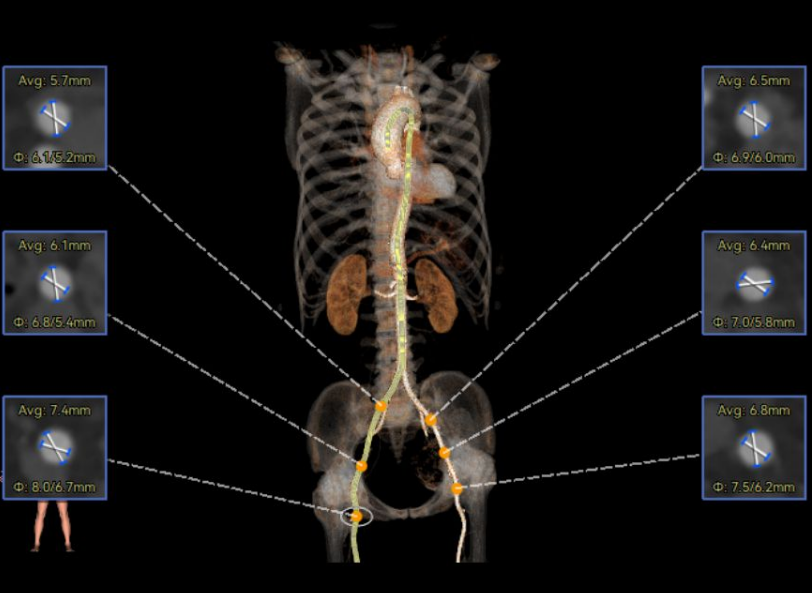

袁祖贻院长 西安交通大学第一附属医院 创新见证中国领跑,数据积累筑牢临床效果 韩克教授 西安交通大学第一附属医院 干瓣技术革新赋能特殊人群治疗,“量体裁衣”筑牢安全防线 患者病史 主诉与现病史:5年前因"血友病,血尿”就诊于当地医院,住院期间行心动超声提示主动脉瓣及二叶瓣畸形,无胸闷气短,无胸痛,咳嗽咳痰,无头晕,恶心呕吐等不适。未予以干预,后规律复查心超,3周前复查心超提示:主动脉瓣二瓣化畸形并重度狭窄,升主动脉内径明显增宽。 既往史:确诊血友病A型40年 术前超声提示:先天性主动脉瓣二叶式畸形,主动脉瓣中度狭窄,升主动脉增宽,左室舒张功能减低,EF73% 术前CT:Type0型二叶瓣,瓣叶增厚无钙化,主动脉瓣环径24.1mm,LVOT23.9mm;双侧冠脉开口高度可,窦部空间可,STJ、升主动脉内径可;预估冠脉低风险;主动脉水平夹角37.1°,主动脉弓角、弓距可;左室内径可;外周入路无明显迂曲,无钙化;双侧股动脉内径可,右侧股动脉低分叉。 手术策略 推荐右侧股动脉为主入路,左侧股动脉为辅入路。右股分叉上方1mm穿刺;仅舒张期时相,需根据球扩结果评估瓣膜尺寸,推荐使用18mm球囊进行预扩;预装AV26瓣膜。 手术过程 在右股动脉穿刺建立通路后,顺利送入大鞘。18mm球囊预扩后评估无腰无漏,后将Prostyle A® AV26瓣膜精准释放于目标位置,术后即刻造影显示无明显反流,无瓣周漏,平均跨瓣压差由术前的100mmHg降至2mmHg,患者血流动力学显著改善,术后超声证实瓣膜启闭良好。 主动脉根部造影 18球囊预扩 定位 稳定释放后脱钩 最终造影形态位置良好 外周血管造影,无血管并发症 术后超声显示无生物瓣位置固定瓣膜功能正常,无瓣周漏。 Prostyle A®预装干瓣——助力临床最优化解决方案 流入端桶状设计:流入端桶状的设计,锚定迅速,有效减少释放步骤,提升植入稳定性; 平衡的收腰设计:二叶瓣患者对瓣膜径向支撑力提出更高要求,Prostyle A®均衡的收腰设计可更好适应二叶瓣解剖,保证了EOA,有效降低了循环崩溃风险,提高瓣膜的耐久性; 预装干瓣 便捷顺安:金仕生物专利抗钙化技术运用纳米技术去除组织内的细胞碎片和磷脂,封闭游离醛基,从根本上阻断了瓣膜钙化的多项因素,显著提升了瓣膜的耐久性;同时,相比较传统戊二醛保存方式,干式存储最大限度的保留心包的亲水亲油平衡,还原组织天然曲柔性,进一步保障了瓣叶开合,保证长期耐久性。 专家简介 袁祖贻 西安交通大学第一附属医院(点击查看专家详细简历) 韩克 西安交通大学第一附属医院(点击查看专家详细简历) · END ·